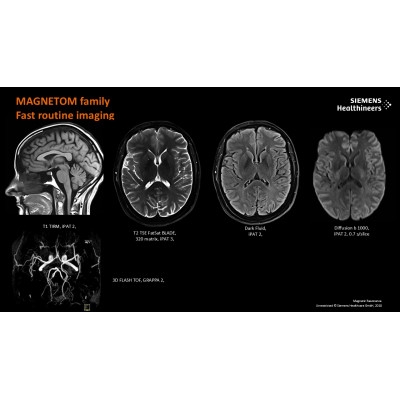

この健診では認知機能テストと脳MRIを行い、AIを用いて海馬(記憶の司令塔)の容積を自動測定し脳の老化具合を算出します。 さらに、脳MRI によって、認知症の原因となりうる「かくれ脳梗塞/脳出血」の存在もわかります。 検査当日に認知症専門医をはじめとした脳神経内科専門医より結果を説明し、生活習慣病予防を中心に今後の認知症予防対策をお伝えします。

※画像はイメージです。